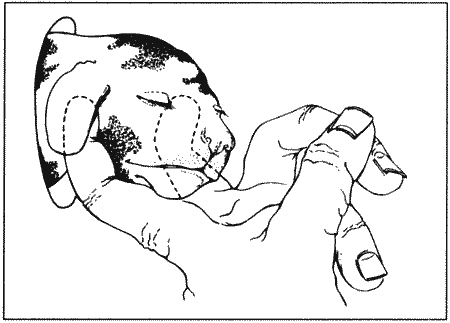

Как правило, у сук наблюдается множественная овуляция; согласно данным гистологических и лапароскопических исследований, в большинстве случаев овуляция происходит в течение 30–48 часов после пика концентрации ЛГ, хотя часть фолликулов овулируют лишь через 96 часов. После овуляции, но до оплодотворения ооциты проходят очередную стадию мейоза. Этот процесс с трудом поддается изучению, однако тщательный хронометраж искусственного осеменения замороженной спермой, взятой от разных кобелей (для упрощения идентификации потомства), приводит к выводу, что созревание ооцитов занимает 2–3 дня. Если сложить их с количеством дней, отделяющих пик концентрации ЛГ от овуляции, то получится, что оплодотворение возможно не раньше, чем через 4 дня, считая от пика концентрации ЛГ; этот день является началом фертильного периода (фиг. 1.2). Ошибки в его вычислении объясняются тем, что признаки эструса наблюдаются уже за 5 дней до начала фертильного периода и продолжаются еще 5 дней после его окончания. Следующие факторы определяют длительность фертильного периода: длительное (до нескольких дней) сохранение жизнеспособности спермы в половом тракте суки; время, необходимое для овуляции и созревания ооцитов (2–3 дня) при сохранении жизнеспособности яйцеклеток (1–2 дня). С учетом этих факторов фертильным следует признать период, продолжающийся от 4-го до 7-го дня, считая от пика концентрации ЛГ. При стандартном подсчете продолжительность беременности составляет от 58 до 72 дней, но если принять за точку отсчета овуляторный пик ЛГ, длительность беременности составит 65 дней с очень небольшими отклонениями.

Оплодотворение

На стадии метэструса происходит развитие эмбрионов; интересно отметить согласованность протекания некоторых основных этапов, предшествующих имплантации, и продемонстрировать их связь с изменениями концентрации прогестерона и эстрадиола (фиг. 1.1). Наиболее целесообразно принять за точку отсчета овуляторный пик ЛГ. Как уже упоминалось, овуляция происходит на 2 день, после чего яйцеклетки проходят период созревания. К 4–7 дню они готовы к оплодотворению. Оплодотворенные яйцеклетки некоторое время удерживаются в маточных трубах, они проходят маточно-трубное соединение и приблизительно на 10 день перемещаются в рога матки. Увеличение соотношения прогестерон/эстрадиол (фиг. 1.1), судя по всему, имеет жизненно важное значение для этого этапа. Бластоцисты локализуются в роге матки вплоть до 13 дня, после чего свободно мигрируют из одного рога в другой до 16 дня, когда набухание эндометрия свидетельствует о том, что имплантация эмбрионов произошла.

Овуляция и оплодотворение

После вязки с фертильным самцом или успешного искусственного осеменения эмбрионы в течение 4–5 дней после оплодотворения развиваются в маточных трубах, затем мигрируют в рог матки, где приблизительно на 12–16 день после повторной вязки (первая необходима для индукции овуляции) происходит имплантация. Перед имплантацией бластоцисты свободно перемещаются в полости матки, мигрируя из одного рога в другой, вероятно, такая миграция обеспечивает равномерное распределение эмбрионов в полости матки. Считая от момента имплантации, беременность продолжается еще 50 дней, таким образом, общая продолжительность беременности составляет около 64 дней (от даты первой вязки). Секреция прогестерона во время беременности — как и в случае ложной беременности — препятствует наступлению эструса.